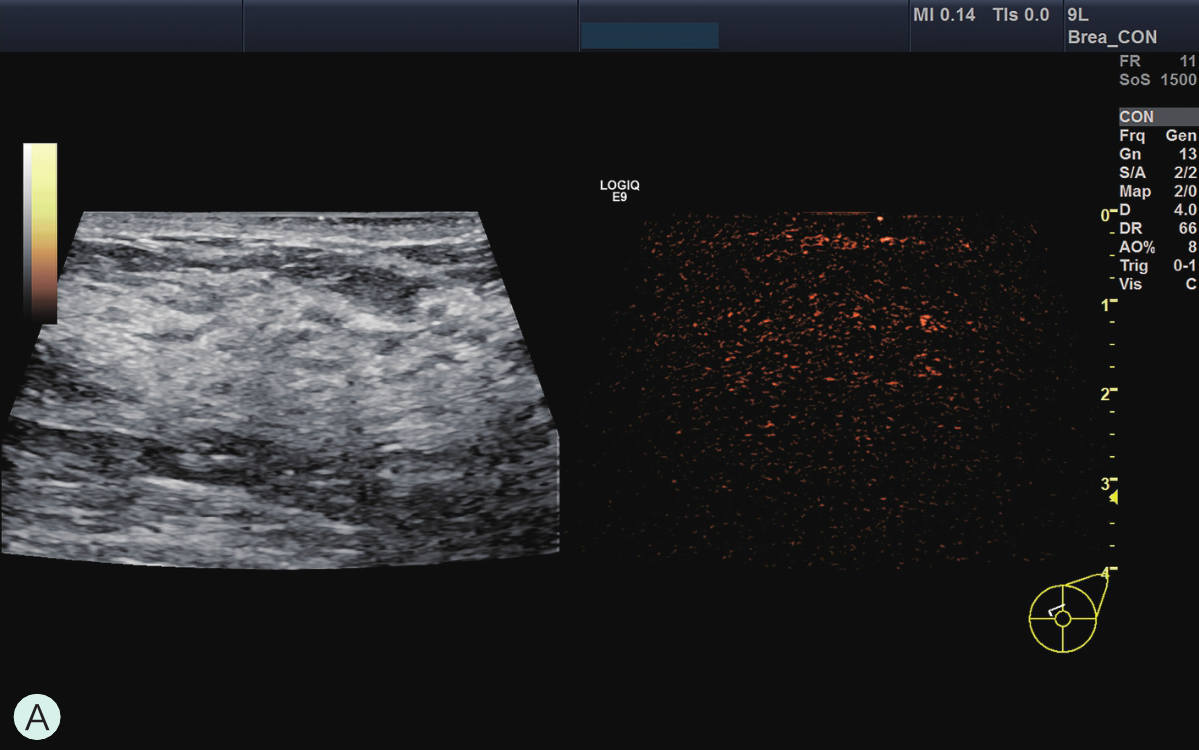

所有具有超声造影功能并支持浅表线阵探头造影的超声诊断仪器均可用于乳腺超声造影检查。由于乳腺超声造影对设备的造影效果、探头选择及参数调节要求很高,故在开展乳腺超声造影前,必须充分论证其造影效果,与设备应用专员共同调节造影参数至乳腺超声造影最佳模式。常规高频线阵探头不能用于乳腺超声造影,而必须选用低频线阵探头。下面将根据笔者所在单位临床工作实际,列举几种超声仪器的乳腺超声造影参数及所用探头供读者参考(图2-1-3~图2-1-7)。

图2-1-3 GE Logic E9乳腺超声造影参数及所用探头

A.GE Logic E9乳腺超声造影参数;B.GE Logic E9乳腺超声造影探头9L